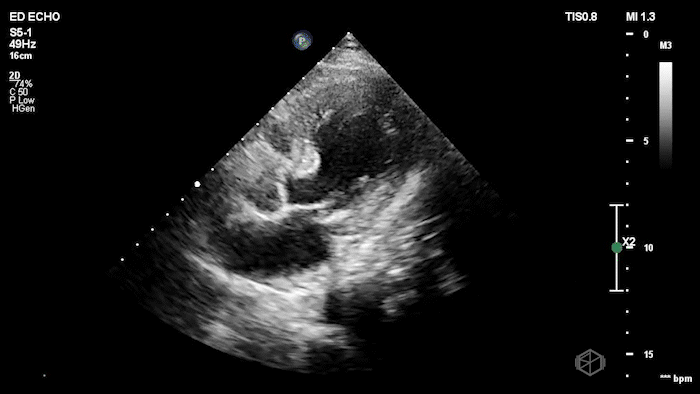

The next SonoProps goes to Dr. Andrew Weinberger. He performed a scan on a mid-70’s female with a past medical history of hypertension, diabetes, hyperlipidemia that had neck pain and then started having chest pain.

His scan showed the following:

The echo shows a reduced ejection fraction with an antero-septal wall motion abnormality.

The patient’s EKG demonstrated an antero-septal AMI.

The patient was taken for a cath and found to have a 100% LAD occlusion. The ejection fraction was 20-29%.

Diagnosis: AMI - Anteroseptal LAD 100%

RWMA shows up early and maps the culprit. In acute ischemia, new regional wall-motion abnormality (RWMA) appears before—or despite nondiagnostic—ECG changes. In STEMI cohorts, EM residents with core ultrasound training detected RWMAs with sens 88% / spec 92% vs comprehensive echo, and territory agreement was substantial—useful for rapidly localizing an LAD-territory infarct like this case. (📚 PMID: 30987914)

High specificity helps you “rule-in” in non-ST presentations, but don’t “rule-out” with a normal scan. In ED chest-pain patients without ST-elevation, POCUS-detected RWMA predicted NSTE-ACS with spec ~93% but sens ~43%—great when present, insufficient to exclude ACS when absent. Treat a normal study as low likelihood, not a discharge ticket (📚 PMID: 38985842).

Residents and EM attendings can learn this and perform well. A 30-minute teaching module improved EP accuracy for WMA recognition from 67% → 87% on test images (pre/post). In clinical ACS cases, residents achieved sens ~86% and attendings/fellows ~85% for RWMA vs cardiology echo (specificity higher in more experienced operators). (📚 PMID: 22046540)

When new RWMA is seen by EPs in patients who don’t meet initial ECG cath-activation criteria, it closely matches cardiology echo findings (EP RWMA vs cardiology echo: spec 96%) and is highly specific for patients who will undergo intervention/CABG (spec ~93%, sensitivity modest). Use ‘new RWMA’—relative to a prior normal echo—as a trigger for expedited cardiology involvement. (📚 PMID: 38205979)

Common pitfalls: Old infarcts/cardiomyopathy can mimic “new” RWMA; paced rhythms/LBBB can confound ECG, making echo relatively more helpful. Suboptimal windows and tachycardia can hide subtle hypokinesis—optimize gain, depth, and frame-by-frame endocardial tracking; when in doubt, label as “possible RWMA—needs cardiology echo.”